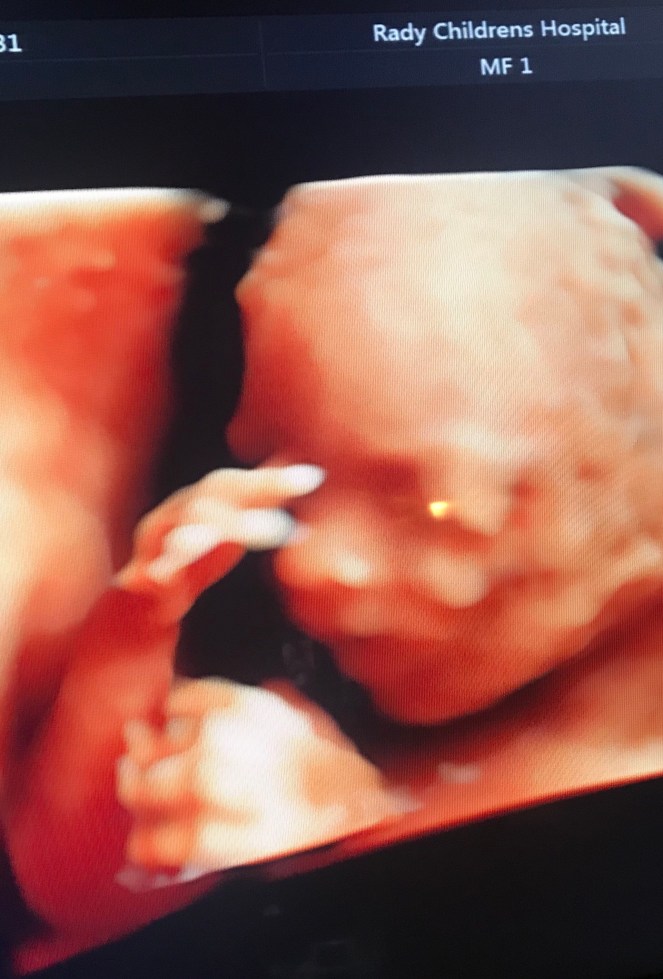

The appointment started off as we expected with the full anatomy scan. We saw every inch of her sweet 10 oz. body and she was active as can be. She kept putting her hands up to her face and everything about her was perfect and adorable. Once that was complete they checked where she was located since we knew she had been on my cervix previously. This part was not what we expected and left us worried.

Baby girl is located directly on my cervix and the specialist thinks she’s not going any where. Normally when someone has placenta previa the baby will favor a side and can migrate up with time. To our surprise she is right in the middle and chances of her moving are slim to none. The doctor explained that I have to stay on bed rest the remainder of my pregnancy and reduce any chance of causing additional bleeding. Any active bleeding could be detrimental to me and her. This was a hard pill to swallow, because it has been a struggle being stuck at home all this time. I’m a busy body and I want to be back at work and be able to go places, but I know this is what is necessary. I’m willing to do whatever it takes to keep our baby girl safe and healthy.